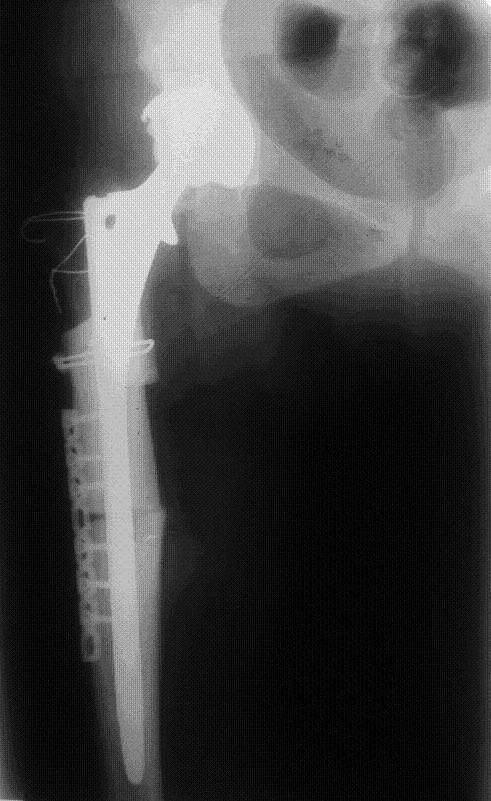

Уважаемый Рашид Муртузалиевич, спасибо за ответы. Вот, что у нас получилось. Большой вертел удалось прификсировать без значительных трудностей (имеется ввиду без большого релиза), однако, по задней поверхности бедра. Почему фиксация по наружной предпочтительнее, ведь и в норме б/вертел несколько смещен кзади? Извините за качество снимка. Позже постараюсь выложить другие.